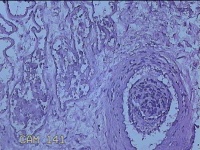

右侧腋窝皮肤

性别

女

年龄

25岁

临床诊断

双侧腋臭

一般病史

发现双侧腋下异味7年。

标本名称

大体所见

灰白暗红色梭形皮肤组织7x2.3x0.8cm一块,表面糜烂,切面灰白暗红色,质软。

图1